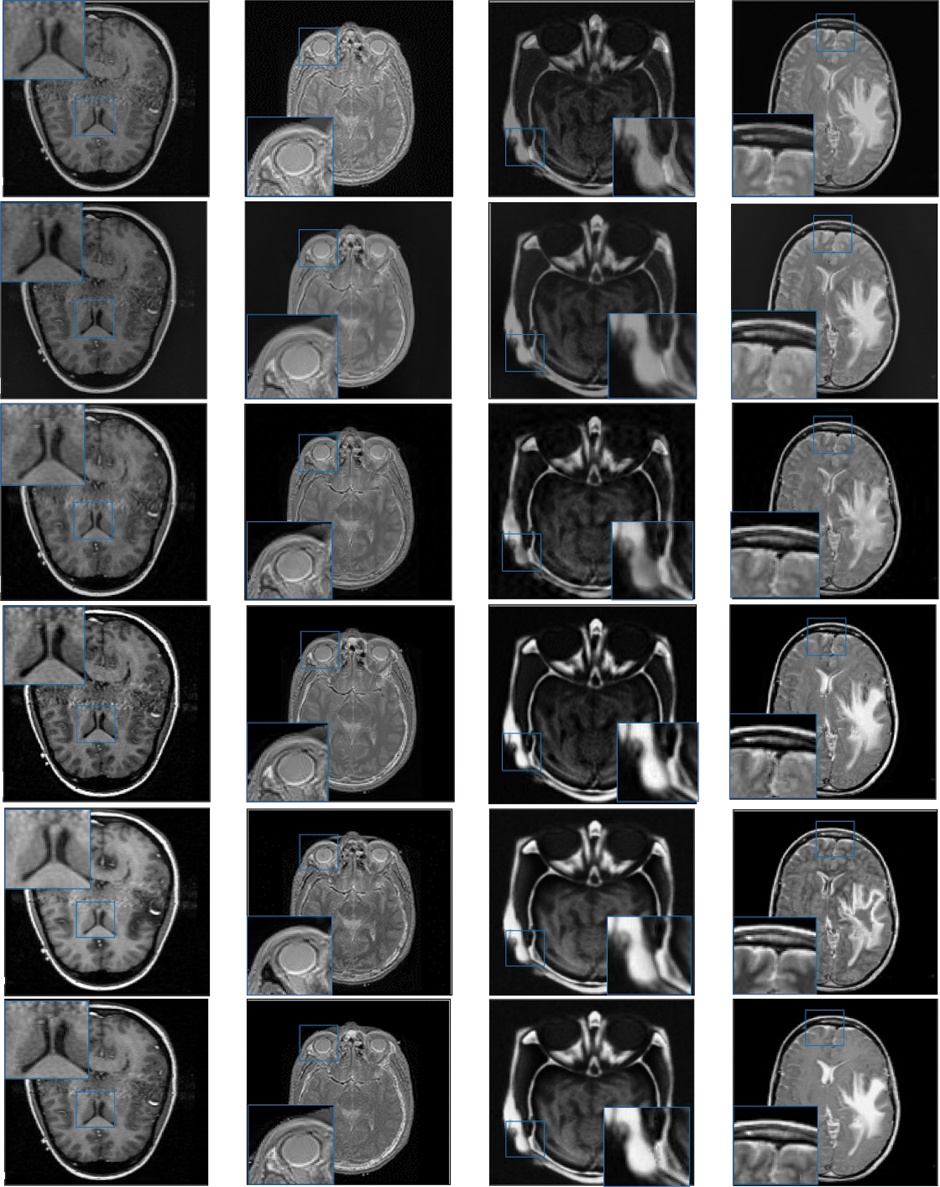

In this study, eight pairs of medical images are employed during the experiments to validate the practicability and feasibility of our algorithm. A total of eight pairs of CT-MRI images are demonstrated in Fig. 2. All these test datasets contain a spatial resolution of 256 × 256 pixels. Further, seven existing comparative methods are utilized for comparison to assess the robustness of our approach, including the adolescent identity search algorithm in the NSST domain (AISA-NSST) [28], the medical image fusion method by deep learning (MIFDL) [40], multi-objective differential evolution based deep neural networks (MDE-DNN [41], geometric algebra discrete cosine metrics (GADCT) [43], medical assistive technology management based on hybrid domain filtering (MATM-HDF) [8], FDGNet [57] and sparse representation and Siamese convolutional neural network (SRSCNN [58]. All the experiments are performed on a PC with an Intel (R) Core (TM) i3-7020 CPU @ 2.3 GHz and 8 GB of RAM using MATLAB 2022a. Following [49], the parameter values are fixed at

Figure 2: Source paired images (A–H): CT-MRI image pairs. Top

To investigate the efficiency of our proposed strategy, this study utilizes eight pairs of publicly accessible images from the Whole Brain Atlas [60]. The eight pairs of medical images in Figs. 2A–2H are represented by Set A to Set H, respectively. Statistical numeric indicators to validate the objective fusion performance is considered, including MI, H, API, CC, AG, API, SF, and SD. Further, in addition to the above metrics, an objective fusion characterization based on gradient details is also considered including

Figure 3: Qualitative results of CT-MRI image pairs on Set (A–D). From top to bottom: results by AISA-NSST, MIFDL, MDE-DNN, GADCT, MATM-HDF, SRSCNN, FDGNet and proposed algorithm

Figure 4: Qualitative results of CT-MRI image pairs on Set (E–F). From top to bottom: results by AISA-NSST, MIFDL, MDE-DNN, GADCT, MATM-HDF, SRSCNN, FDGNet and proposed algorithm